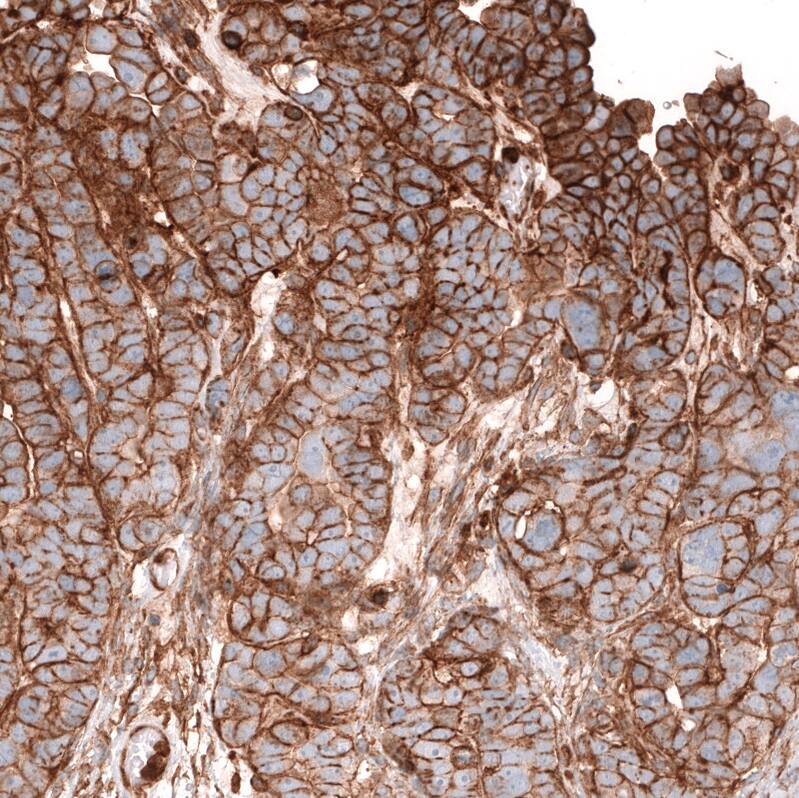

Immunohistochemistry-Paraffin: IGFBP-2 Antibody (CL13563) [NBP3-24568]

Staining of human pancreas shows strong membranous positivity in exocrine glandular cells.